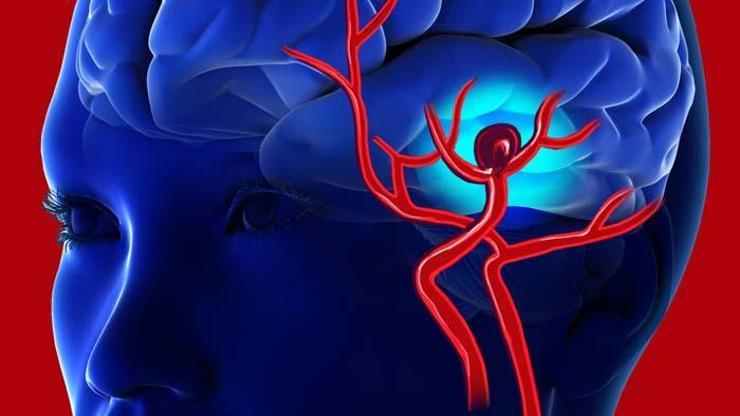

Vücudumuzun farklı bir bölgesinde oluşan pıhtının, oluştuğu yerden koparak kan dolaşımına karışması ve beyne ulaşması durumuna beyne pıhtı atması denir. Beyne ulaşan pıhtı, beyindeki kan damarını tıkar ve beynin kan dolaşımını engellerse inme gelişir.

İnme, beyin damarlarının tıkanması veya kanaması sonucunda gerçekleşir. Beyin damarlarının tıkanması ise orada oluşan bir pıhtı nedeniyle veya vücudun başka yerinde oluşan pıhtının beyne atması nedeniyle oluşabilir. Beyne pıhtı atması olarak bilinen durum budur.

Beyin damarlarını tıkayarak inmeye neden olan pıhtı, vücudun pek çok farklı bölgesinden gelebilir. En sık ise kalp ve boyun damarlarından gelir. Kalbin ritim bozukluklarından biri olan atriyal fibrilasyon, beyne pıhtı atmasında en önemli risk faktörüdür.

Beyin damarları yalnızca kan pıhtısı nedeniyle tıkanmaz. Kemik kırıklarında, kemik iliğinden kana karışan yağ damlacığı veya çeşitli nedenlerle kan damarlarına giren hava baloncukları da beyin damarlarında tıkanıklığa neden olabilir.